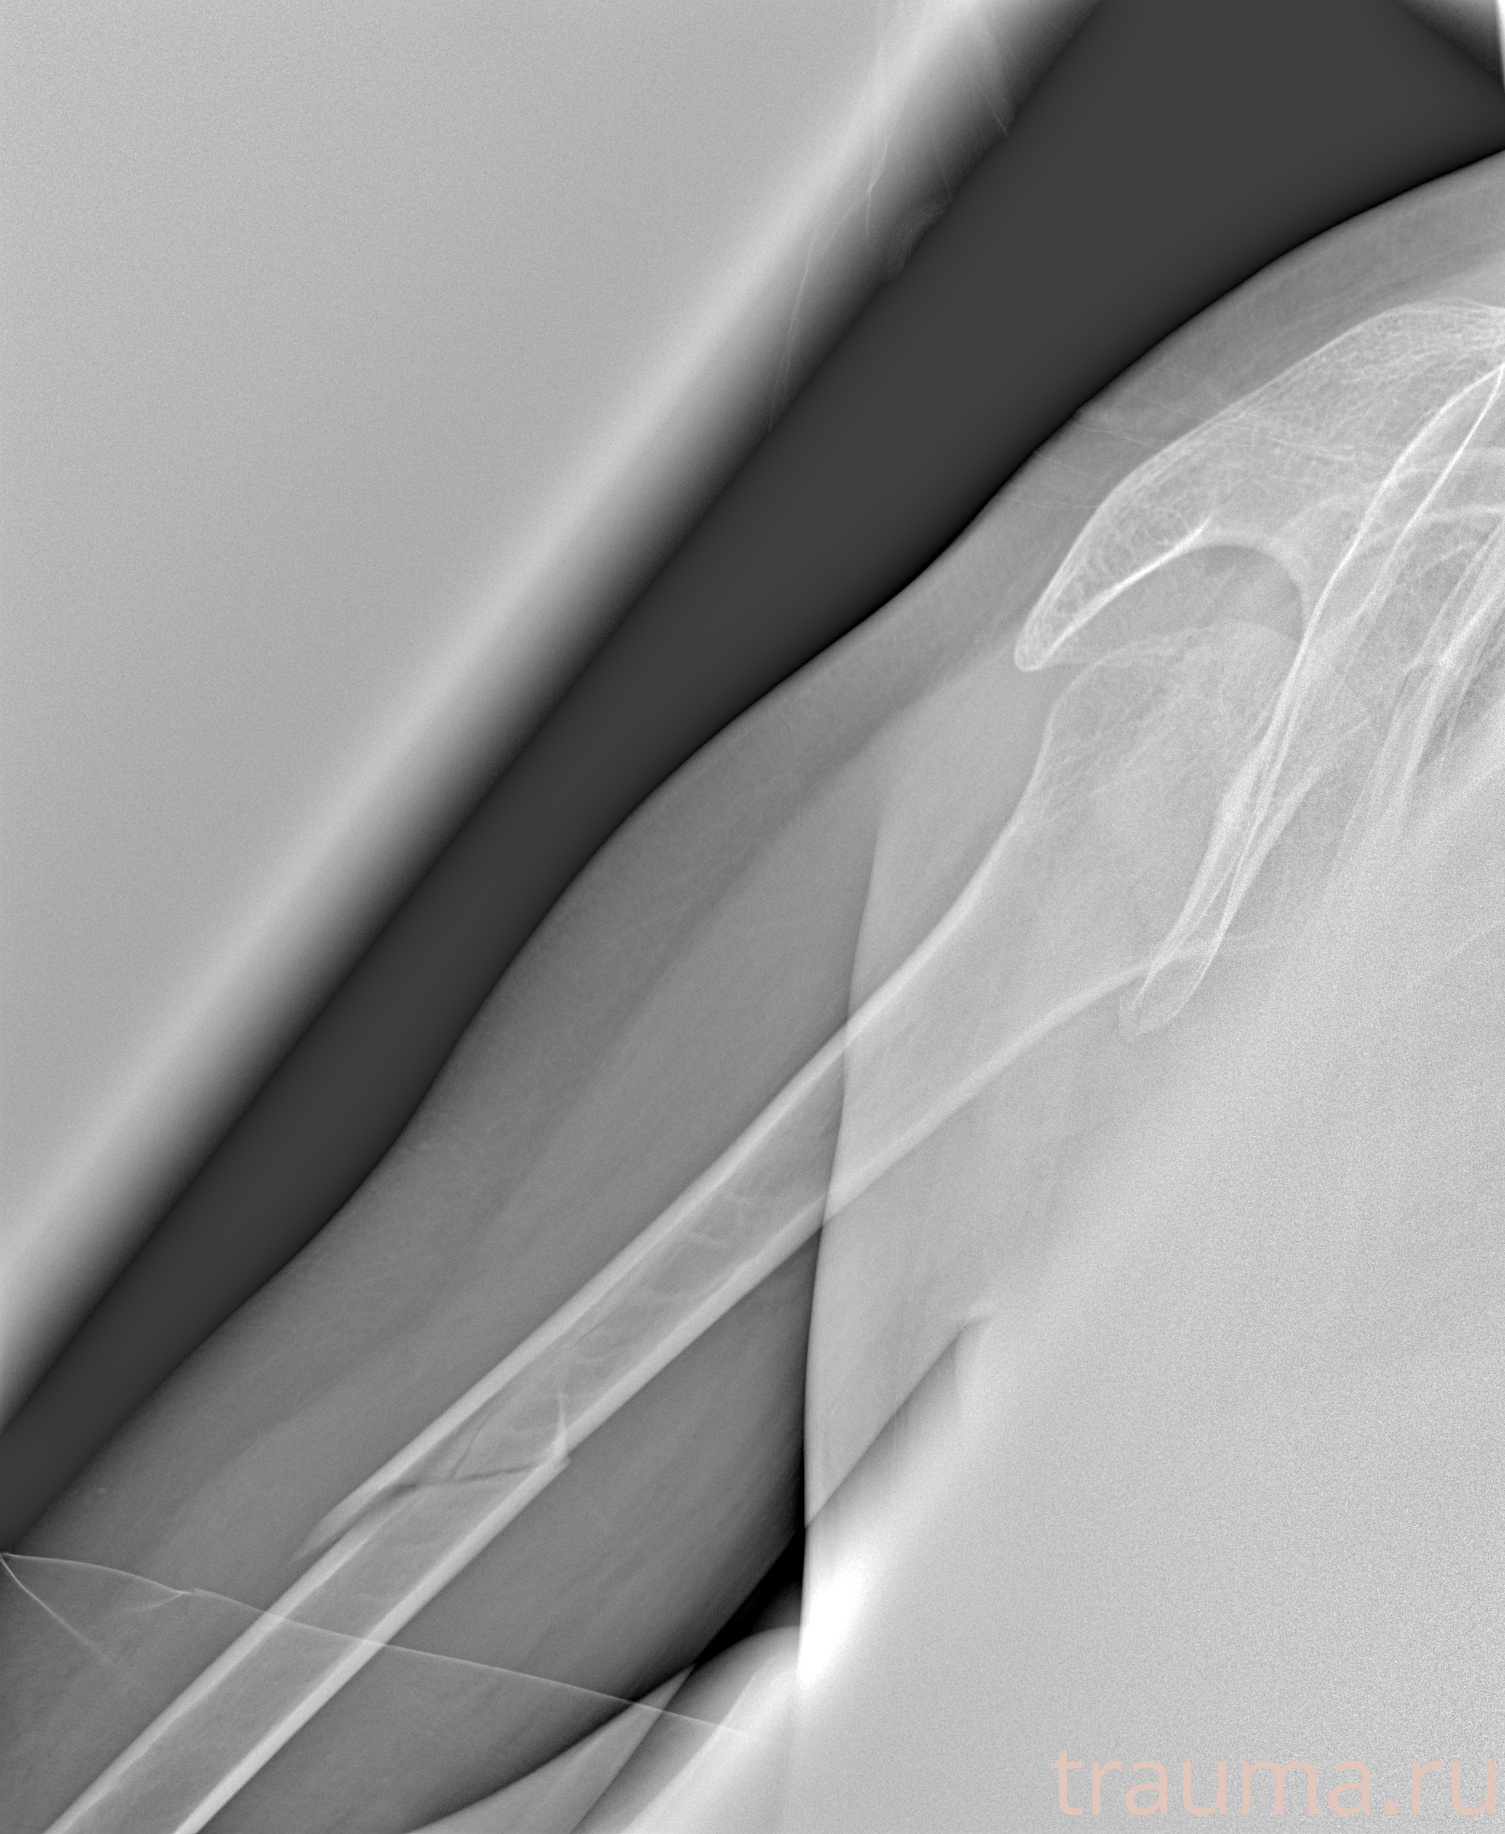

Рентгенограммы

Рентген на дому: по вашему адресу приезжает врач-рентгенолог, травматолог-ортопед с мобильным рентгеновским аппаратом, проводит диагностику травмы или заболевания, делает необходимые рентгенограммы, дает рекомендации по дальнейшему лечению. Получить качественные снимки в домашних условиях возможно благодаря уникальной методике, разработанной МосРентген Центром для института  Склифосовского